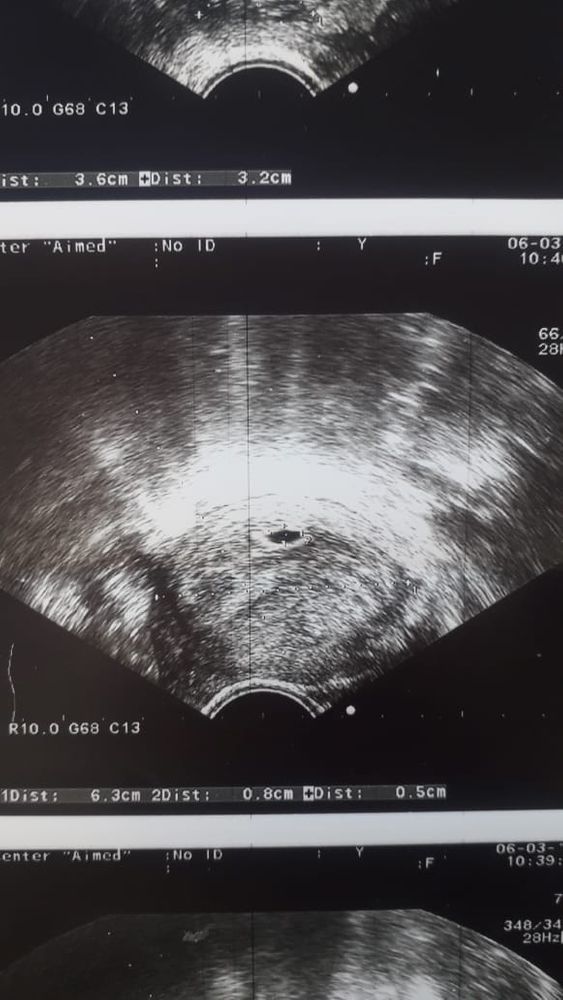

24 дпп узи

24 дпп узи 24 дпп какой размер пя?